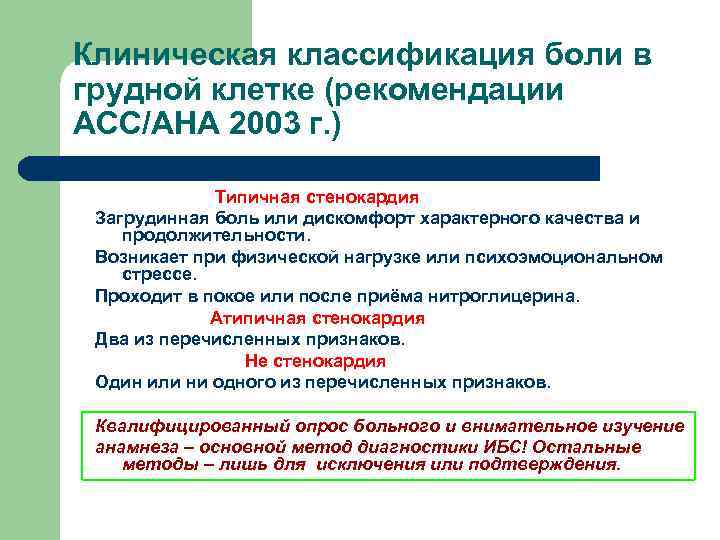

Клиническая классификация боли в грудной клетке (рекомендации АСС/АНА 2003 г. ) Типичная стенокардия Загрудинная боль или дискомфорт характерного качества и продолжительности. Возникает при физической нагрузке или психоэмоциональном стрессе. Проходит в покое или после приёма нитроглицерина. Атипичная стенокардия Два из перечисленных признаков. Не стенокардия Один или ни одного из перечисленных признаков. Квалифицированный опрос больного и внимательное изучение анамнеза – основной метод диагностики ИБС! Остальные методы – лишь для исключения или подтверждения.

Не стенокардия: l l l Острая, прокалывающая боль Боль, зависящая от дыхания, положения тела (попросить замереть на несколько секунд) Боль, сохраняющаяся несколько часов Боль выше нижней челюсти и ниже эпигастрия Зона боли – под кончиком пальца в левой половине грудной клетки Обратить внимание на жестикуляцию!